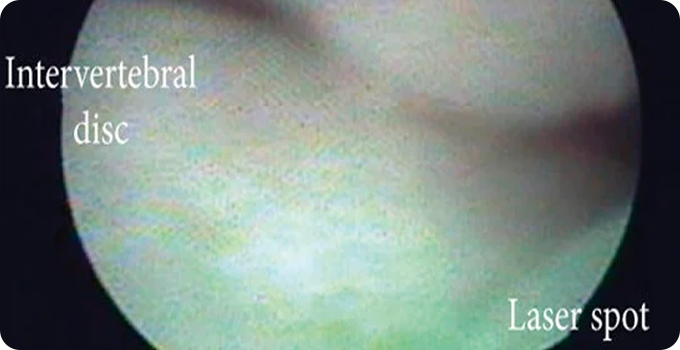

최소절개 척추내시경 사진

최소절개 척추내시경

내시경을 통해 돌출된 디스크를 제거하거나 신경 압박을 해소하는 최소침습적 수술입니다. 절개 부위가 작아 회복 기간이 짧고 통증이 덜한 것이 장점입니다. 디스크로 인한 통증, 감각 이상 등을 직접적으로 해결할 수 있습니다. 고난도의 기술이 요구되며, 환자 상태에 따라 적합성을 전문의와 상의해야 합니다.